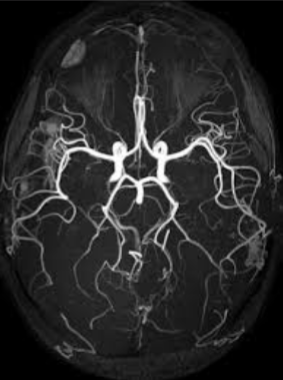

What imaging is seen here of the cranial vessels?

MRI